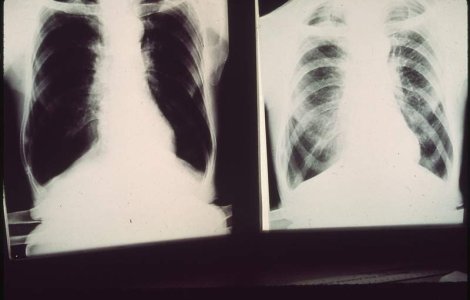

Simplul act de a respira ar putea fi un mod major de transmitere a tuberculozei, sugerează un studiu dat publicităţii marţi, care ar putea modifica profund strategiile de luptă împotriva acestei boli, tradiţional centrate pe tuse, principalul său simptom.

Romania este tara din Uniunea Europeana cu cele mai multe cazuri noi de tuberculoza inregistrate, incidenta fiind de 6,5 ori mai mare ca in UE, au informat specialistii de la Spitalul de Pneumoftiziologie Sibiu, care au organizat joi o conferinta de presa, cu ocazia Zilei Mondiale de Lupta impotriva acestei grave maladii.

Specialistii din domeniul medical trag un nou semnal de alarma in ceea ce priveste incidenta, riscurile si tratarea tuberculozei in Romania, care, in ciuda eforturilor depuse, continua sa ramana a sasea tara ca incidenta a tuberculozei in Regiunea Europa a Organizatiei Mondiale a Sanatatii (OMS).

Romania raporteaza anual aproximativ 13.000 de noi cazuri de pacienti, fiind tara europeana cu cea mai ingrijoratoare statistica din acest punct de vedere.